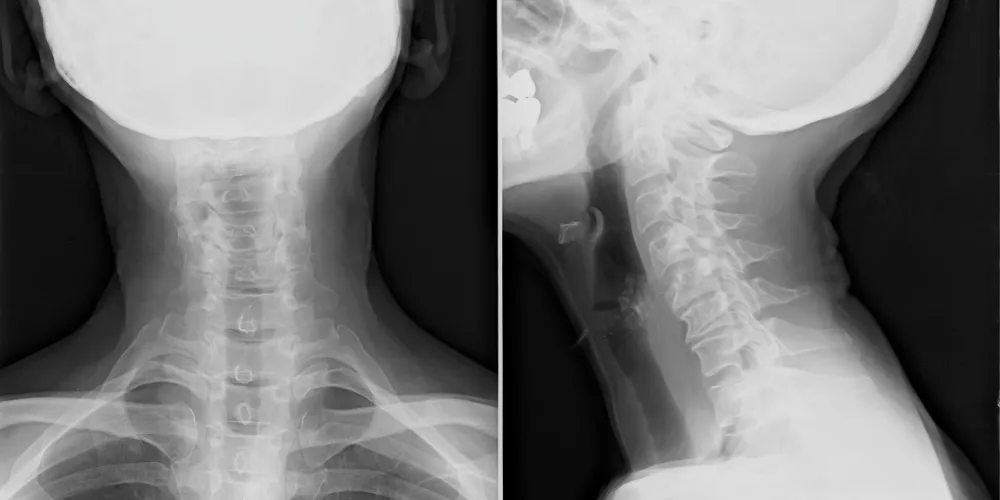

Full-spine x-ray films allow us to precisely analyze the entire structure of your spine and correlate these biomechanical findings with your entire examination.

This enables the most precise adjustment to achieve the best corrective results.

X-ray’s also rule out any congenital malformations, disease processes, and / or fractures.